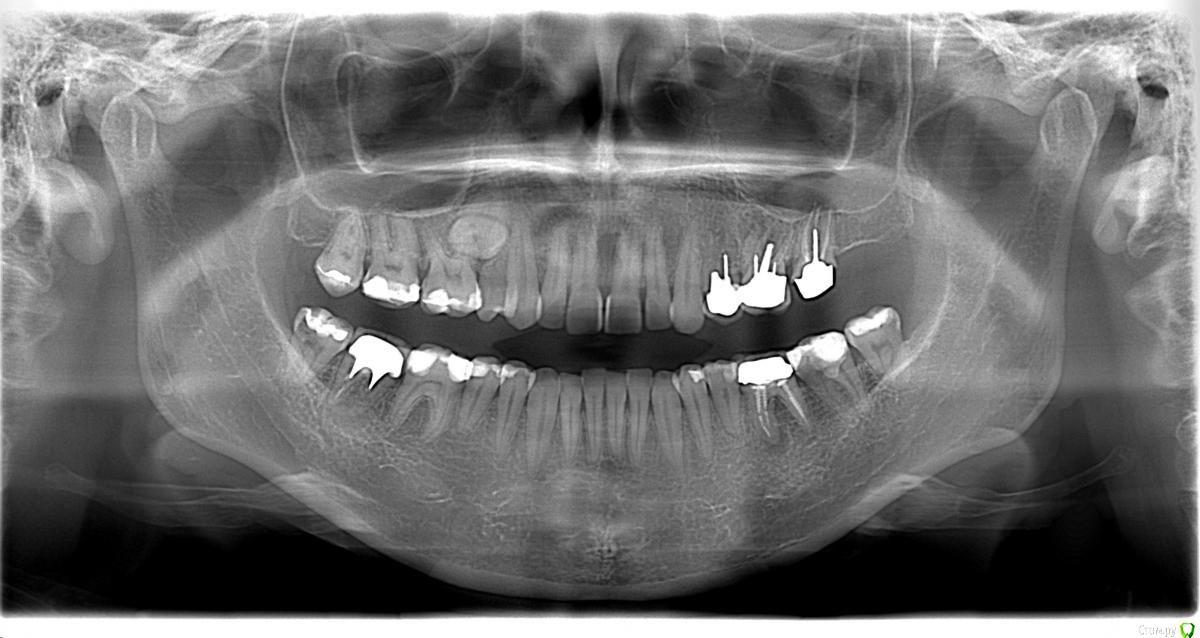

Opdihatop Опубликовано 16 апреля, 2017 Поделиться Опубликовано 16 апреля, 2017 Здравствуйте, коллеги! Что вы думаете по поводу этого случая? Объективно: вертикальный рост, первый костный класс. Незначительная протрузия резцов в/ч, нормальный наклон резцов н/ч. 15 зуб ретенирован. Значительное сужение в/ч, сужение н/ч.Вопросов 2: 1) Тянуть ли 15 зуб? 2) Планирую расширять при помощи SARPE, что делать с образовавшимся местом (которое и так сейчас уже есть)? Мне кажется такие большие реставрации будут некрасивыми. Ссылка на комментарий

Brigita Опубликовано 16 апреля, 2017 Поделиться Опубликовано 16 апреля, 2017 (изменено) Здравствуйте, коллеги! Что вы думаете по поводу этого случая? Объективно: вертикальный рост, первый костный класс. Незначительная протрузия резцов в/ч, нормальный наклон резцов н/ч. 15 зуб ретенирован. Значительное сужение в/ч, сужение н/ч.Вопросов 2: 1) Тянуть ли 15 зуб? 2) Планирую расширять при помощи SARPE, что делать с образовавшимся местом (которое и так сейчас уже есть)? Мне кажется такие большие реставрации будут некрасивыми.1) а куда его?2)Реставрации передних зубов имеется ввиду? Не такой большой промежуток, можно и реставрацию, если виниры не может позволить. расширение на SARPE - в таком возрасте без хирургии маловероятно, Вы же сами знаете, получите зубоальвеолярное небольшое расширение и наклон. Такой тонкий биотип, что там еще с кортикалкой будет. Мосты спаянные, вкладки. Чтобы узнать положение 5го надо КТ сделать, где у него корень - пойдет ли. Он видимо в небной костиА вообще - отдайте ее ортопедам. Она сама то что хочет? Изменено 16 апреля, 2017 пользователем Brigita Ссылка на комментарий

Brigita Опубликовано 16 апреля, 2017 Поделиться Опубликовано 16 апреля, 2017 Черные треугольники заполнить и рецессии убрать. я вот чего то не понимаю наверно.. где треугольники, которые она хочет убрать? я вижу диастему, трему 22-21, кариес 11-12, многочисленные рецессии, плохие ортопедические коронки, неправильно выполненные вкладки ( а может правильно? я не ортопед), скученность нижних зубов. А вообще вот интересно - в каком возрасте максимально возможно расширение на SARPE, у кого какой опыт? Ссылка на комментарий